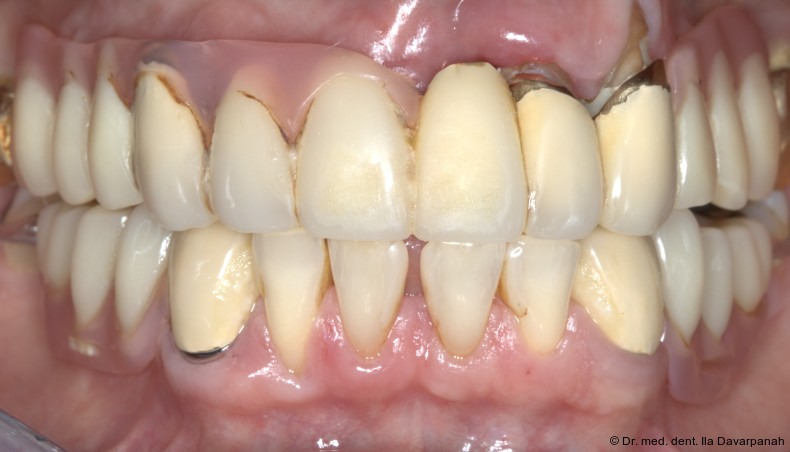

Ein 62-jähriger Patient stellte sich mit bestehendem Zahnersatz im Oberkiefer vor und äußerte den Wunsch nach einer implantatprothetischen Versorgung. Drei Restzähne im Oberkiefer waren erhaltungswürdig. Nach differenzialdiagnostischer Analyse wurde eine abnehmbare, teleskopierende Versorgung geplant. Die Zähne 17 und 27 wurden mit provisorischen Kronen aus Polymethylmethacrylat (PMMA) versorgt, spielten jedoch keine tragende Rolle in der Gesamtplanung.

Nach strategischer Pfeilervermehrung zur polygonalen Abstützung wurden vier Pfeiler für die geplante Prothesenspanne definiert. Die Versorgung begann mit vorbereitenden Maßnahmen wie einem digitalen Mock-up zur Bestimmung der horizontalen und vertikalen Kieferrelation (Abb. 1 + 2).

Eingliederung der Reise- und Definitivprothese

Nach Verkleben der sekundären Galvanokappen mit dem Tertiärgerüst verbleiben die Primärzirkonkappen im Mund. Um dem Patienten auf Basis dieser Pfeiler eine Interimsversorgung geben zu können, wird eine sogenannte Reiseprothese mit der Ästhetik und Funktion der finalen Versorgung hergestellt, welche auch als Referenz hierfür dient (Abb. 18+19).

Die definitive Prothese konnte im dritten Behandlungstermin problemlos eingegliedert werden. Es waren lediglich minimale okklusale Anpassungen erforderlich (Abb. 20–24).